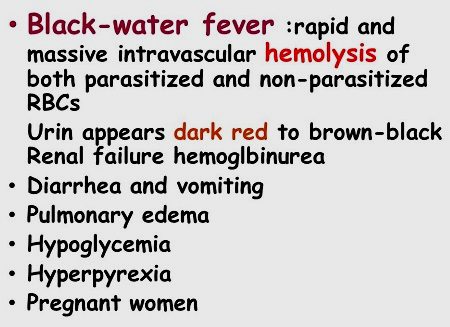

Pioneering achievement: curing blackwater fever

Albert Schweitzer was finally able to cure the dreaded

blackwater fever (destruction of red blood cells, e.g.

by high doses of quinine) by injecting 3% saline

solution under the skin of the thighs (letters from

Lambarene, p.575-576)